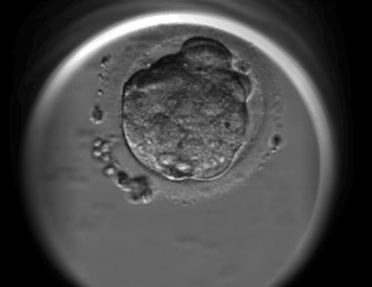

讓你們看看我的胚培盛世美顏

首先讓我們來了解一下這個傳說中的“囊胚”。囊胚指的試管是內(nèi)部產(chǎn)生囊胚液、囊胚腔的嬰兒養(yǎng)胚胎。具體來說的話,胚胎在培養(yǎng)到第三天,我們稱為卵裂期胚胎,繼續(xù)培養(yǎng)如果能進一步發(fā)育,到了第四天后,其細胞數(shù)量超過64個以上,細胞團的中間出現(xiàn)一個腔隙,且細胞完成了第一次分化,此時的胚胎我們稱為囊胚。而所謂囊胚培養(yǎng)則是目前培養(yǎng)胚胎體外培養(yǎng)技術所能指“胚胎體外培養(yǎng)”的最后階段,它通常指的是卵子受精后的第5-6天。原來這就是我們第二次看胚胎的時候啊!